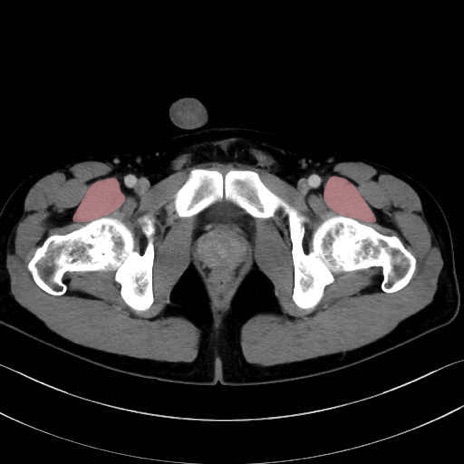

内閉鎖筋 (Obturator internus)

外閉鎖筋 (Obturator externus)

大腿方形筋 (Quadratus femoris)